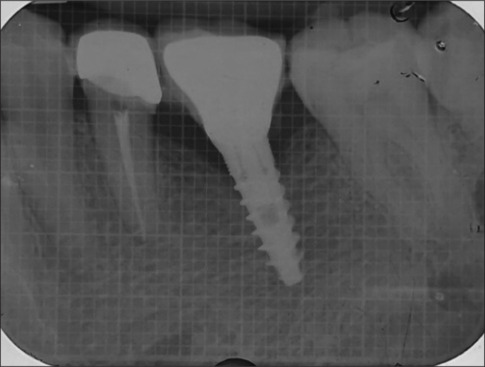

Purpose: The present investigation assessed the success of narrow diameter implants (NDI) supporting a single crown in the molar region of the jaw.

Materials and methods: A total of 40 patients (>20 years) requiring implant supported crown in the molar region were recruited. A total of 20 patients received NDI (3.5 millimeter (mm), and another 20 received standard diameter implants (SDI), ≥3.75 mm. Crestal bone level, probing depth (PD), implant mobility, and bleeding on probing (BOP) were recorded at baseline, 6, and 12 months.